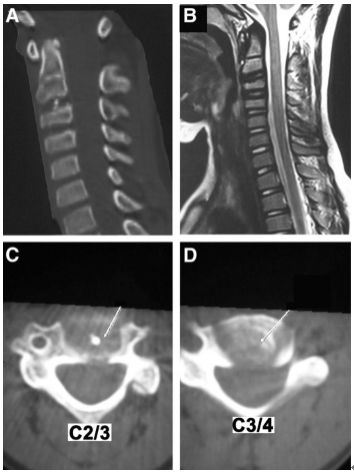

图:C2-3儿童颈椎间盘钙化合并后纵韧带骨化虽然本病可以发生在从新生儿到青春期, 但其发病高峰为6~10岁,男性多于女性,发病部位以颈椎间盘最为多见,胸椎次之,腰椎最少,颈椎中以C6-7和C3-4节段最为常见。一般为单一节段的椎间盘钙化,少数病例也可有两个部位的椎间盘钙化,部分病例可伴有后纵韧带骨化。另外,部分病例可出现神经刺激症状,且在影像检查中不仅可以看到椎间盘异常征象,还可显示肿块侵入椎管,甚至压迫脊髓,特别是合并后纵韧带骨化的病例,椎管侵占率往往大于50%。

图:8岁女孩,因颈腰痛伴左上肢放射痛2月余就诊,颈椎侧位片、CT和MRI表现与上述病例类似。

图:给予保守对症治疗(具体不详)1月后症状消失。6个月时随访可见钙化的椎间盘和后纵韧带都消失了。